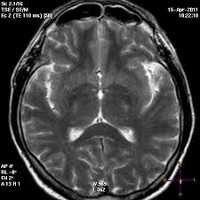

поражение белого вещества мозга при лейкоэнцефалопатии

С помощью КТ и МРТ можно обнаружить гиперинтенсивные очаги поражения в белом веществе мозга. При подозрение на инфекционную форму, электронная микроскопия позволяет выявить в мозговой ткани частицы вирусов. Иммуноцитохимический метод - выявление антигена вируса. Люмбальную пункцию проводят при повышении белка в СМЖ. При данной патологии в ней выявляют также лимфоцитарный плеоцитоз.